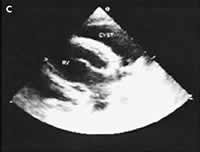

1名20岁的海军学校学生,在军队体格检查时被发现其胸部X线片异常,而来心脏科门诊。其自诉无症状,体格检查结果亦正常。X线胸片(图A)显示在右心膈角区有一平滑的密度边缘,它部分地遮盖了右心边界。CT扫描显示(图B),紧靠心脏的右边界有一均质的平滑病灶,其间没有分隔和钙化。大小约5.0 cm×4.4 cm×7.0 cm,而心脏和大血管均正常。超声心动图(图C)对该病灶进行了进一步评价,改良右胸骨旁角度证实存在一个充满液体的心包囊肿。由于该军校学生没有症状,并且心包囊肿是良性的,所以医师决定对其临床随访观察。